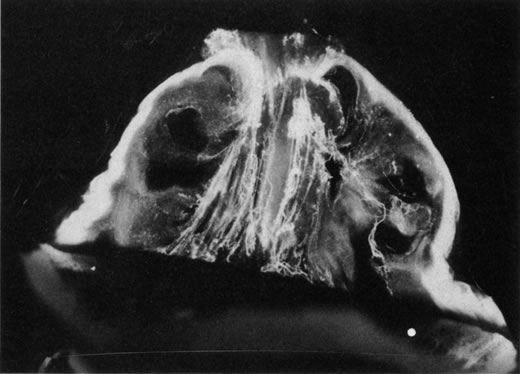

Vitreous is one of many connective tissues in the body. Collagen is one of the most important structural molecules in all connective tissues. Thus, it is of interest to consider parallel phenomena occurring in the vitreous and connective tissues elsewhere, especially as related to collagen. For example, Gartner67 pointed out the similarities between the intervertebral disk and the vitreous, in which age-related changes with herniation of the nucleus pulposus was associated with presenile vitreous degeneration in 40% of cases. He proposed that a generalized connective tissue disorder resulted in disk herniation and presenile vitreous degeneration in these cases. Based on these findings, Gartner likened herniation of the nucleus pulposus in the disk to prolapse of vitreous into the retrohyaloid space by way of the posterior vitreous cortex following posterior vitreous detachment (see Fig. 9).

Fig. 9. Vitreomacular traction. Vitreous can remain attached to the macula even in the presence of posterior vitreous detachment. In such cases, vitreous can extrude through the premacular vitreous cortex and fibers can insert into the macula. B, C, and D are an artist's rendition of this phenomenon. A demonstrates vitreous extrusion into the retrohyaloid space in a specimen from a middle-aged human. (Adapted from Jaffe NS: The Vitreous in Clinical Ophthalmology. St. Louis, CV Mosby, 1969; and Jaffe NS: Vitreous traction at the posterior pole of the fundus due to alterations in the posterior vitreous. Trans Am Acad Ophthalmol Otolarynogol 71:642, 1967.)

Lindner111 and Jaffe112 described that in some cases of PVD, there is herniation of vitreous through the vitreous cortex of the posterior pole. As previously mentioned, Gartner67 drew an analogy between this phenomenon and the herniation of the nucleus pulposus in the intervertebral disks of the spine. When a PVD involves herniation of the vitreous into the retrovitreal space by way of the premacular vitreous cortex, there can be persistent attachment to the macula and traction (Fig. 9).113